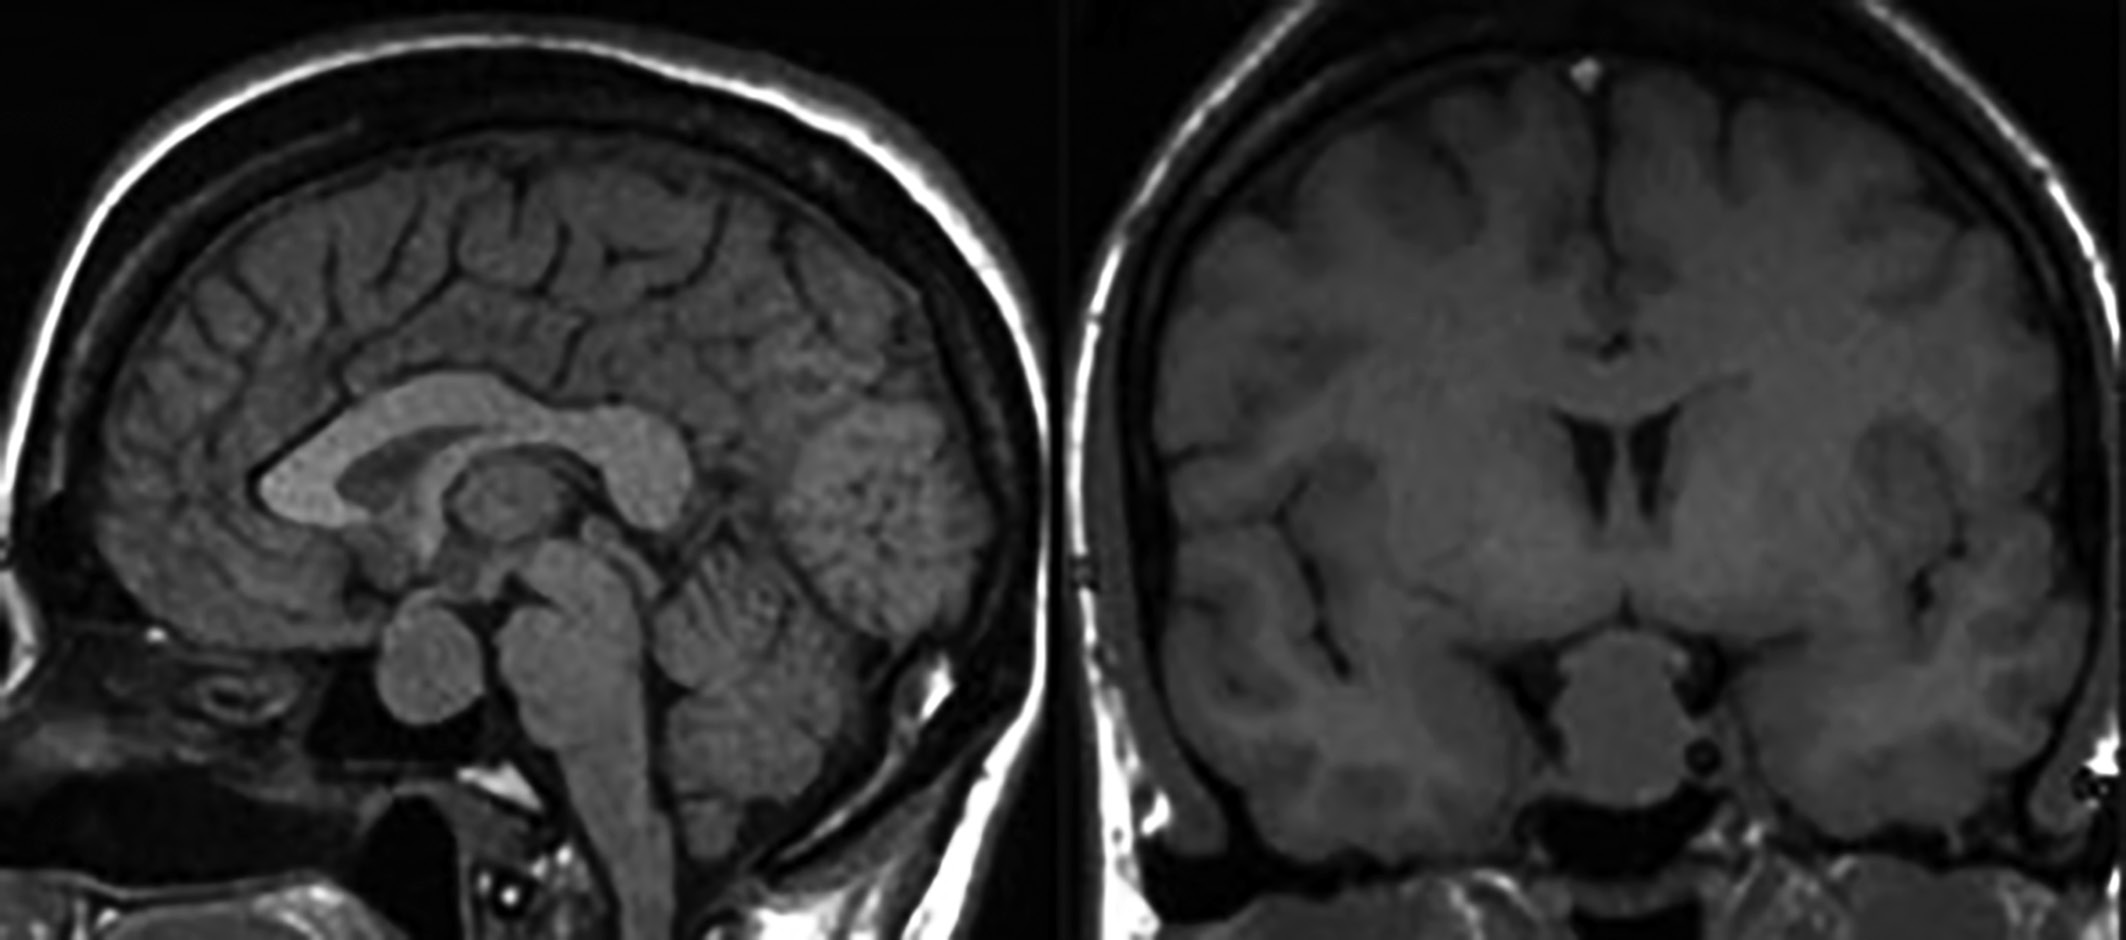

8. Figure 8. Endosuprasellar somatotropinoma. On sagittal (A) and frontal (B) MRI scans in T1-weighted mode, a hypointense tumor is detected. | |